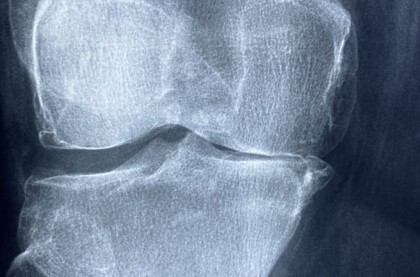

Osteoartrita, cea mai frecventă afecțiune musculo-scheletică din lume, distruge cartilajele articulațiilor, provocând durere și limitând mișcarea. Deocamdată nu există un tratament complet, iar tratamentele variază de la prescrierea de analgezice până la înlocuirea chirurgicală a articulației cu una sintetică. Cu toate acestea, în unele situații intervenția chirurgicală nu permite pacientului să revină la o gamă completă de mișcare.

foto: Image by Manuel Gonzalez Reyes on Pixabay